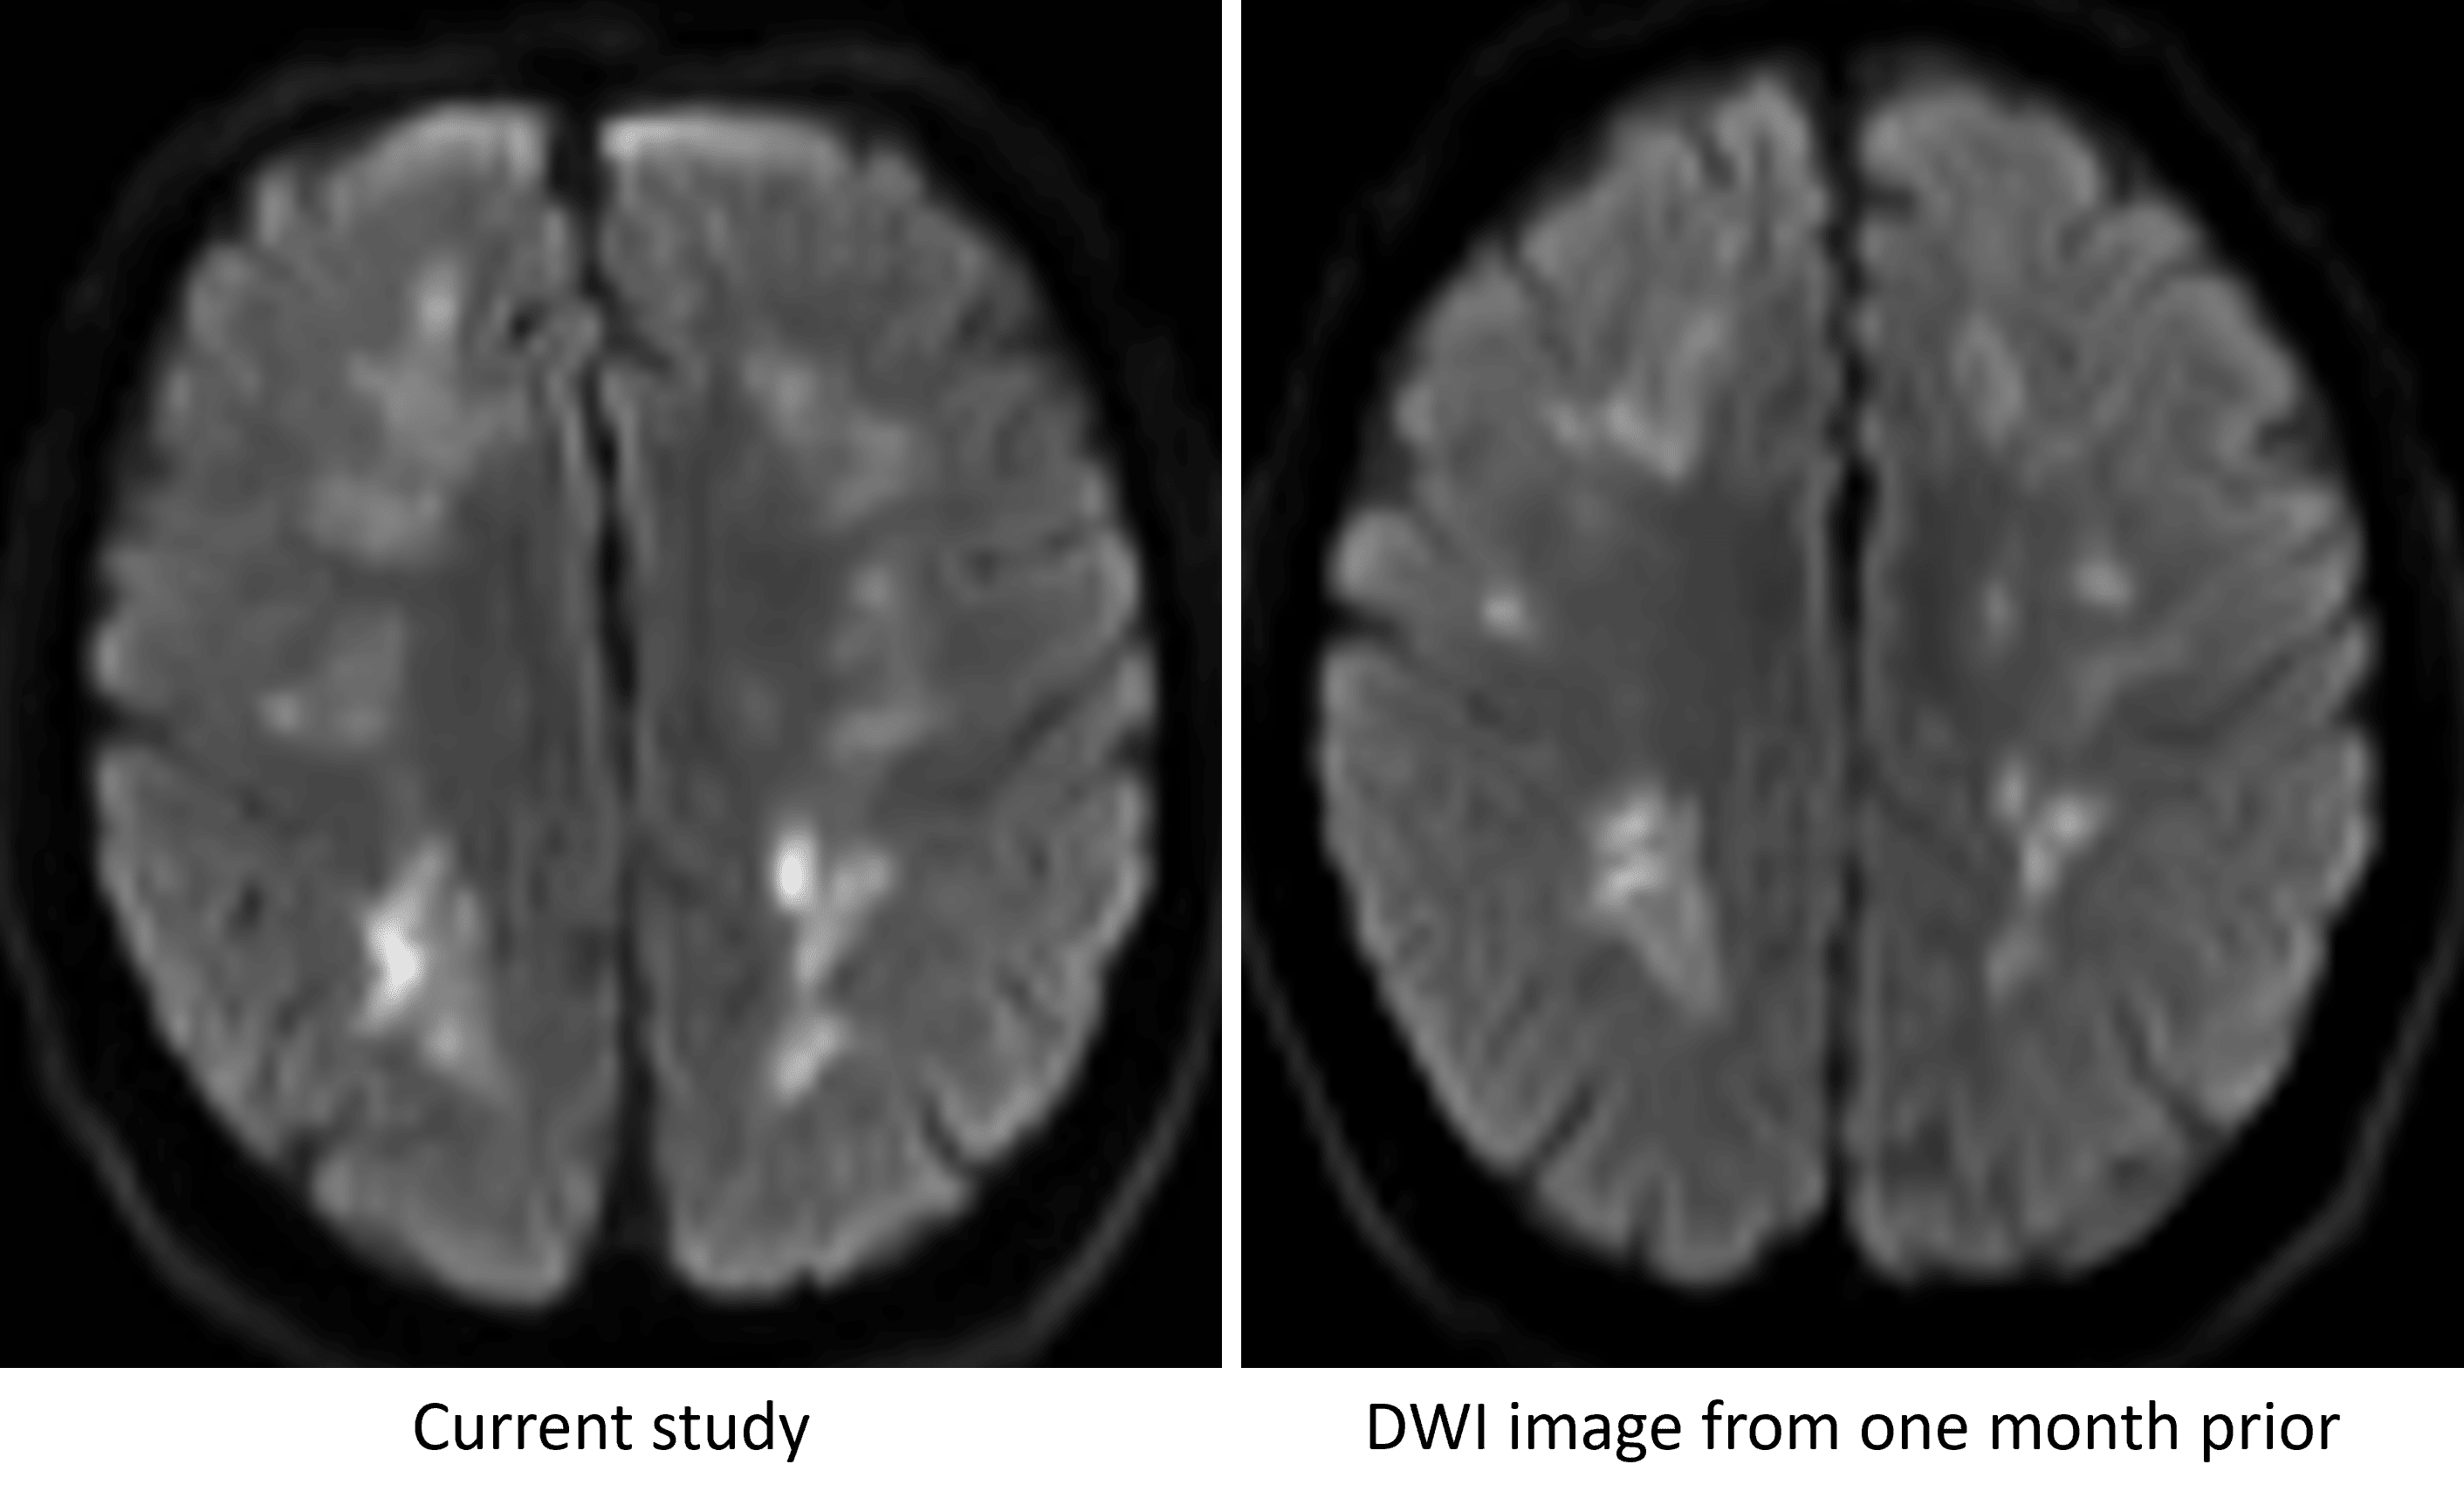

Persistence of restricted diffusion in the cerebral white matter over a one month interval, which is not typical for ischemic infarcts resulting from a single event.

• Corresponding patchy restricted diffusion